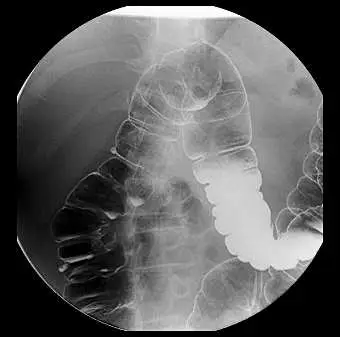

20.下圖所顯示之大腸鋇劑攝影影像,患者採取那一種攝影姿勢及其主要目標是那一區域?

- 解剖構造確認:影像為大腸雙重對比鋇劑攝影。圖中可見一段大腸呈現明顯的彎曲處,且位於影像的左半側(即病患的右側)。

- 特徵辨識:在該彎曲處的上方,可清楚觀察到一個大面積且均勻的軟組織假影,此為肝臟(Liver)的陰影。由於脾彎曲(Splenic flexure)通常解剖位置較高且角度較銳利,而此彎曲位置較低且頂端被肝臟壓迫,因此可明確判定此部位為肝彎曲(Hepatic flexure,或稱右結腸曲)。

- 影像對比與擺位效應:影像中肝彎曲被空氣良好地充盈,且黏膜表面均勻附著鋇劑。此彎曲處的升結腸與橫結腸並無重疊,呈現完全展開(opened up)的狀態,顯示這是一張針對肝彎曲所拍攝的特定擺位影像。